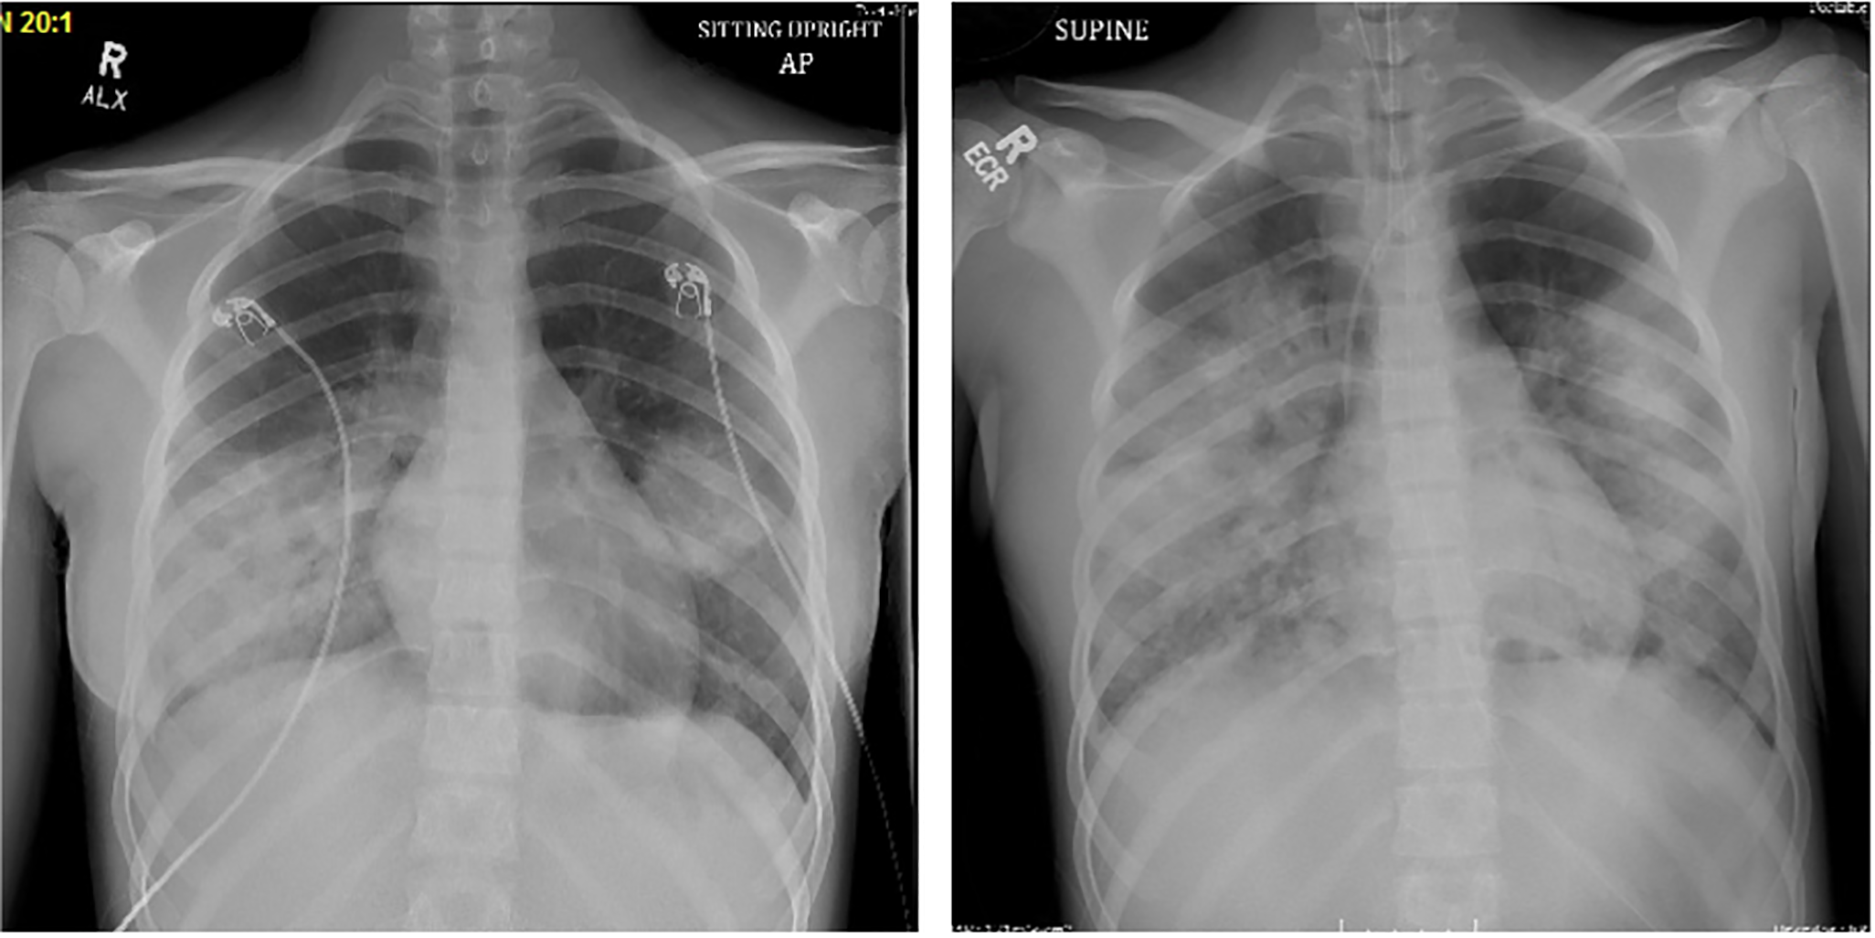

A previously healthy 14-year-old female presented to the Emergency Department with cough, shortness of breath, and fever to 38.8°C. The patient reported 12 days of cough and rhinorrhea with symptomatic worsening five days prior to presentation, including: fatigue, nausea, vomiting, diarrhea, abdominal pain, and headache. The patient was fully vaccinated (including against SARS-CoV-2), did not have known exposure to sick contacts, and denied any recent travel from her home in Southern California. She had no underlying immunodeficiency nor was she receiving immunosuppressive therapy. She denied exposure to unpasteurized dairy, water parks, freshwater swimming, or ocean swimming. She endorsed occasional remote hot tub use, with no use in the 2 weeks prior to presentation. The patient was admitted and initiated on supplemental high flow oxygen due to hypoxia and increased work of breathing. Initial laboratory studies were significant for a C-reactive protein of 31.4 mg/dl (ref 0–0.99 mg/dl), a procalcitonin of 29.57 ng/ml (ref <0.5 ng/ml), leukocytosis with neutrophilic predominance (WBC 17.3, 90% neutrophils, 7% bands), and a respiratory multiplex PCR panel (ePLEX, Genmark Diagnostics, Carlsbad, CA) from the nasopharynx positive for human rhinovirus/enterovirus. A chest radiograph (CXR) on admission was notable for bilateral opacities consistent with multifocal pneumonia (Figure 1). She was initiated on ceftriaxone for empiric coverage of CAP. On hospital day (HD) 2, due to persistent high fever (40°C) and worsening respiratory status, clindamycin was added for coverage of methicillin resistant staph aureus (MRSA) and anaerobic pathogens. Local MRSA isolates demonstrate 84% sensitivity to clindamycin.

Figure 1

Chest radiograph on HD 1 (left). Chest radiograph on HD 4, post-intubation (right).

On HD 3, the patient exhibited worsening respiratory failure necessitating transfer to the Pediatric Intensive Care Unit and bilevel positive airway pressure (BIPAP). She had worsening pleural effusions on CXR and clinical signs of fluid overload thus what started on intermittent intravenous furosemide. Ultimately, her hypoxia and work of breathing necessitated intubation on HD4. At that time, she met clinical criteria for severe ARDS with an initial oxygenation index (OI) of 30 and a maximum OI of 39, a PaO2/FiO2 ratio of 90, with a maximum positive end-expiratory pressure (PEEP) of 24. Adjuncts such as inhaled nitric oxide and prone positioning were required for refractory hypoxemia. Bronchoalveolar lavage was not performed for diagnostic purposes due hypoxia and the severity of her ARDS. She was hemodynamically stable during this period with intermittent use of low dose epinephrine infusion to support blood pressure and diuresis. On HD 3 levofloxacin was added to the antimicrobial regimen of ceftriaxone and clindamycin to cover for atypical organisms.